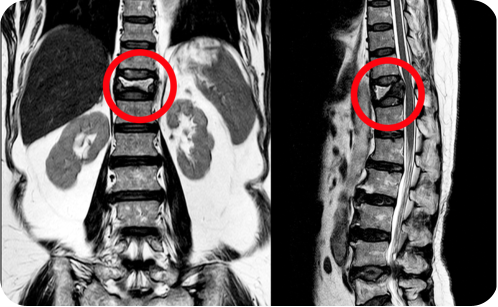

Herniated disks occur when part of the nucleus, the gel at the center of the disk, pushes back into the spinal canal. The injury to the disk can cause neck or low back pain. In some cases, it can also compress the nerves, causing pain, numbness and/or weakness in the arms or legs.